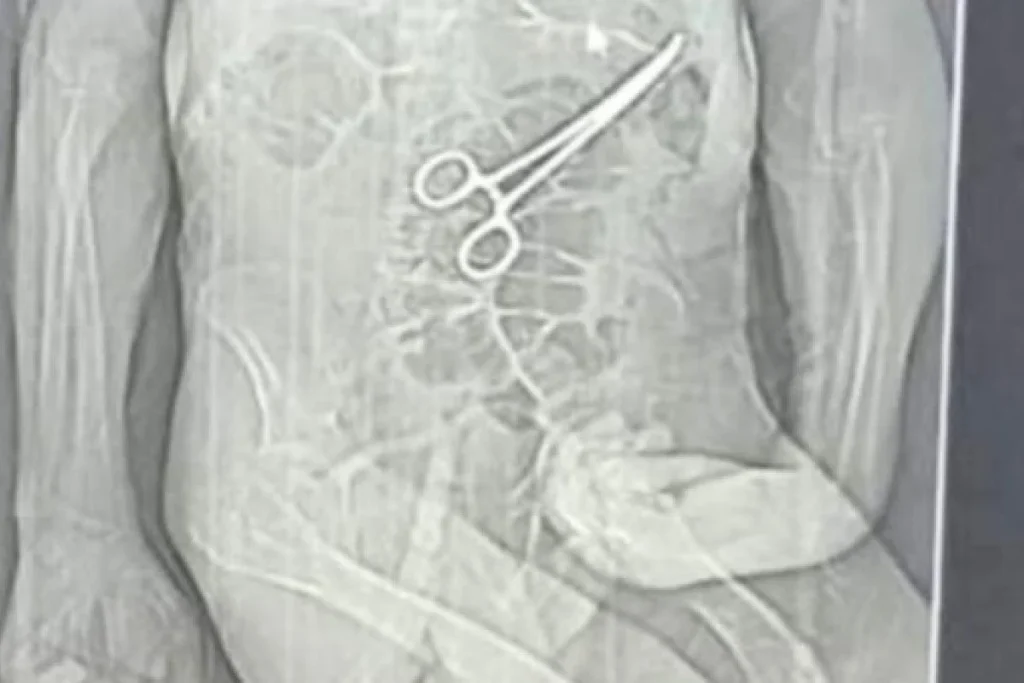

Segundo os parentes, a equipe médica não informou sobre a existência do objeto estranho identificado no abdômen do paciente. A descoberta, segundo o relato, teria ocorrido apenas após a divulgação de uma reportagem em uma rádio local, que apresentou imagens de uma tomografia indicando a pinça.

Foi nesse período que uma tomografia identificou, de acordo com a Secretaria de Saúde, “um corpo estranho na cavidade abdominal” do paciente. Diante do achado, uma nova cirurgia foi realizada em 11 de dezembro com o objetivo de remover o objeto.